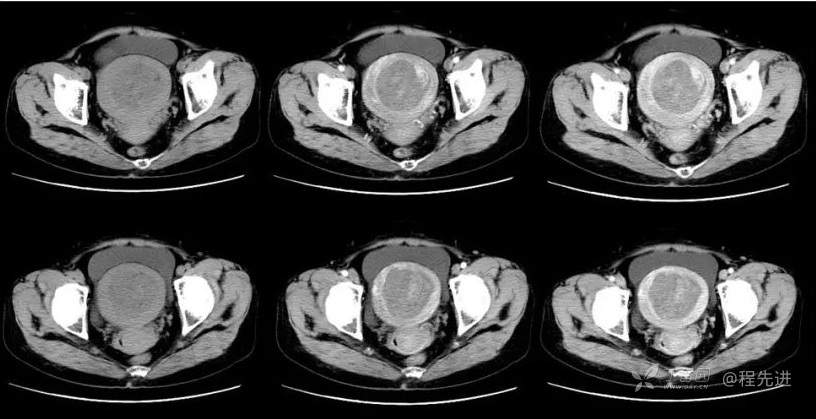

B超:中腹部混合回声肿块,性质待定